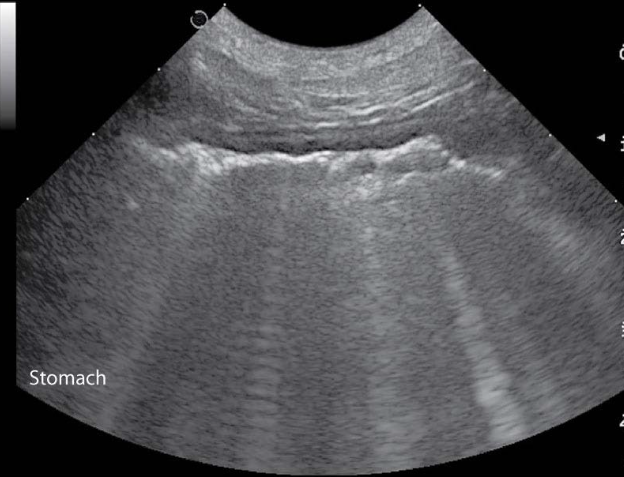

GI tract

stomach is caudal to liver on midline in canine and to the left in feline